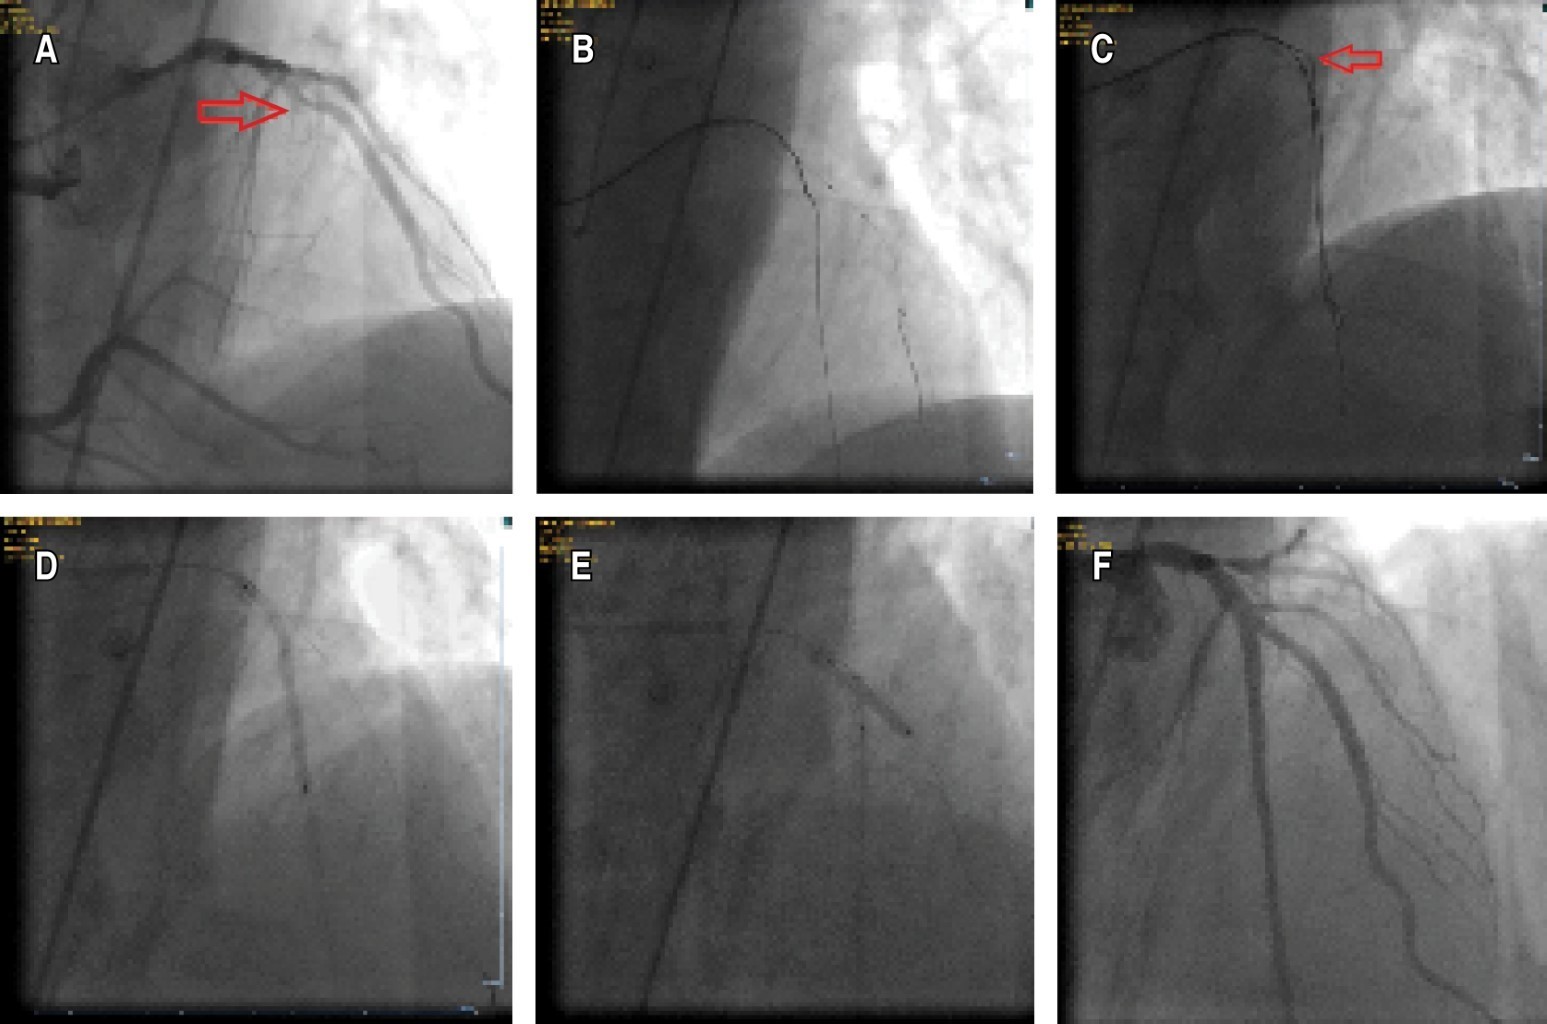

A 66-year-old male with typical angina and a history of failed CTO percutan was referred to our CTO tertiary center for retry. Echocardiography revealed an ejection fraction of 45%. MRI study demonstrated viability in the LAD region. Coronary angiography revealed a long LAD CTO over 20 mm with heavy calcification (Figure 1A). The J-CTO score was four since the first attempt in another center had failed due to the inability of the wire passage.1 The cap of the CTO was semi-ambiguous. The wire was able to be advanced through the highly calcified lesion with the support of a microcatheter, but the microcatheter and even low-profile balloons could not be advanced despite good backup with 7 fr femoral access and an EBU catheter in place (Figure 1B). First of all, the microcatheter was exchanged with a more supportive one, and the calcified lesion was tried to be drilled. The second step was using a guide extension catheter in order to increase support. Upon failure, an anchor balloon was inflated in the septal branch. A blimp scoring balloon was used in combination with an anchor balloon and deep-seated guide extension.2 Leopard crawl technique and grenadoplasty were also tried, but both failed.3 The other options were the STAR technique, which will probably lead to the loss of many side branches, and the retrograde approach, with a low chance of success due to unfavorable collaterals. If we wanted to use a rotaablator, we first had to pass a rotawire through the microcatheter, and since the microcatheter could not be advanced, there was a risk of losing the original wire, which was in the true lumen due to the long distance of the CTO. Moreover, the patient refused.

Since the balloon uncrossable lesion was covered with a high calcium burden, cracking the calcification with a balloon advanced over a subintimal hydrophilic wire was another option. A fielder XT-A guidewire was advanced around the CTO lesion in the subintimal area (Figure 1C). A 2112 mm balloon was inflated at 8 atm over the wire in the subintimal area to crack the calcification from outside. After extraluminal plaque modification, the subintimal wire and the balloon were withdrawn. A microcatheter was then advanced with the support of an anchor balloon over the original true lumen wire (Figure 1D). Then the procedure was successfully completed with balloon predilatation and stent implantation (Figure 1E-F).

Figure 1